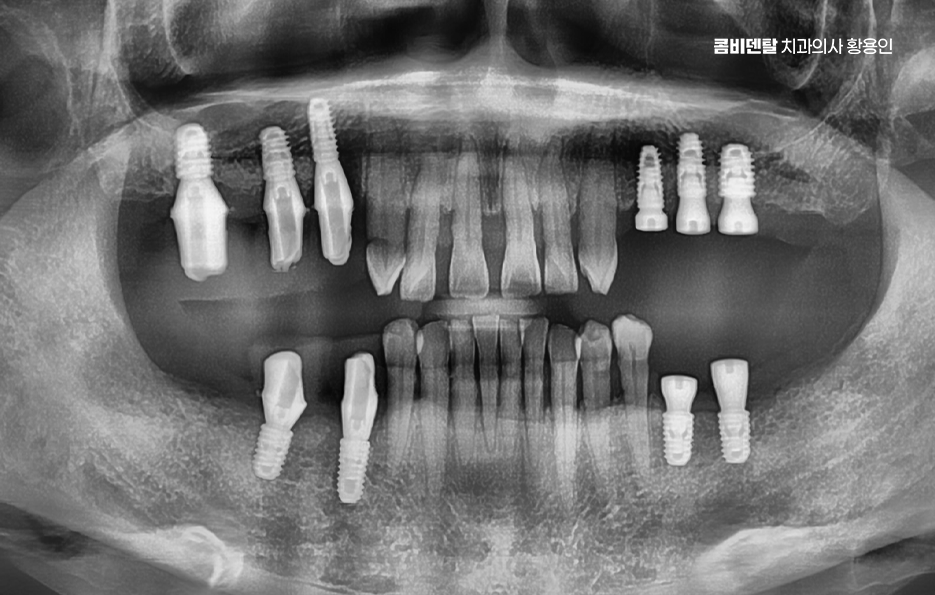

그렇다면 어금니 발치 후, 임플란트를 잘 받기 위한 방법은 뭐냐 하면 첫 번째는 시기를 놓치지 않는 것인데 발치 후 3개월 내에는 임플란트를 심는 게 이상적이며 사실 요즘은 경우에 따라 ‘즉시 식립’이라고 해서 발치 당일에 임플란트를 심는 경우도 많아지고 있기 때문에 발치와 함께 임플란트 치료 계획을 세우는 것이 이상적이라 할 수 있어요

나에게 맞는 치료를 하기 위해서는 정확한 진단과 설계가 중요하며 CT 촬영 등을 통해 신경 위치, 뼈의 양, 두께 등을 정밀하게 진단한 다음, 교합과 치열 구조에 맞는 위치에 임플란트를 심는 게 중요한데 잘못된 위치에 심어지면 오래 쓰기 어렵고, 나중에 통증이나 염증이 생길 수 있었어요.